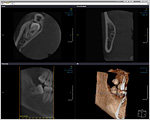

詳細な検査と正確な診断のため、

1.被爆量を最小限に抑えた歯科用CT装置とデジタルレントゲン

ー 歯科用CT装置 ー

ー デジタルレントゲン ー